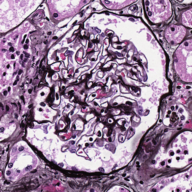

Image datasets in digital pathology applications often consist of consecutive slides stained differently, each staining providing specific information on the same region of interest (see Figure 1, first row). Even though differently stained slides appear very different, there is often a significant amount of consistent information between them. For example, they may both share the same counterstain (e.g. haematoxylin), or they may highlight different parts of the same structure.

The analysis and integration of information from different stainings is usually performed with reference to a specific organ, structure, or pattern observed in the tissue. For example, to diagnose pathologies such as breast cancer or kidney allograft rejection it is necessary to study the inflammatory micro-environment of the organ. In these cases, the relevant information is the distribution of immune cells (e.g. macrophages or lymphocytes) in relation to important structures of the organ, such as glomeruli for the kidney, or lobules for the breast.

Objects to be segmented, e.g. glomeruli, are generally easily identified between stainings as globally they exhibit the same structure and texture, see Figure 1. It should therefore be possible to bias the network to learn stain invariant features. This work investigates this possibility by modifying the data presented to the network in an unsupervised manner. Borrowing domain adaptation terminology, herein the staining used for training and validation is referred to as as the source staining (irrespective of any transformations), and the stainings to which the network are applied as target stainings.

N.B. the intention is to present plausible colour profiles to the network. This does not necessarily correspond to biologically relevant image information but is explored for any potential for the tested staining modalities. Potential limitations are addressed, e.g. in Figure 1 the bright red colour (chromogenic reaction used to detect CD34, a marker of blood vessel inner lining) could be successfully transferred but it is not localised as in the original image.

Next is a strategy to extract biological information that is consistent across different stainings—the haematoxylin counterstain. Despite this biological plausibility, it does not result in good results. Indeed, the haematoxylin transformed images vary greatly between the different stainings (see Figure 1, second row). Several factors may explain this: 1) haematoxylin’s concentration relative to the primary stain may vary from one staining to another, resulting in different shades of blue and fixation amount; 2) as a counterstain, haematoxylin may become mixed with another stain in structures that are targeted by both. These result in a color mixing that is in practice not perfectly unmixed by a color deconvolution algorithm.